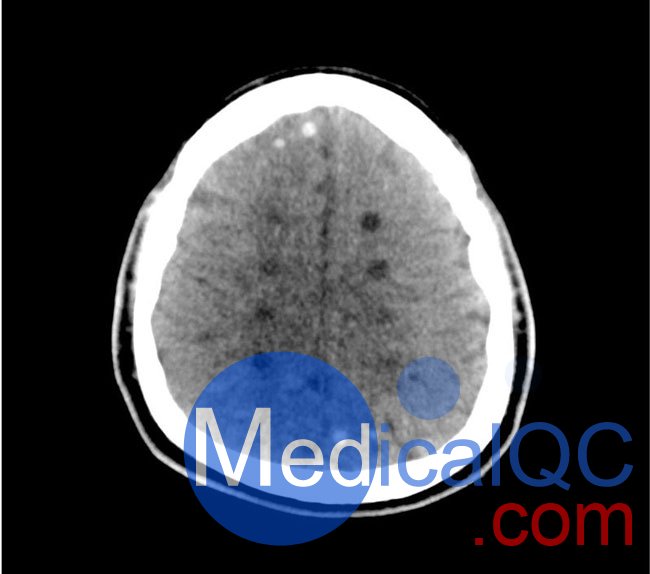

中風(fēng)

• 高密度大腦中動(dòng)脈 (MCA) 和左側(cè)基底神經(jīng)節(jié)消失

• 大腦中/后動(dòng)脈 (MCA/PCA) 和大腦前動(dòng)脈/中動(dòng)脈 (ACA/MCA) 領(lǐng)域的分水嶺梗死

• 8 個(gè)不同年齡的腔隙性梗死

出血

• 蛛網(wǎng)膜下腔出血(2個(gè)地區(qū))

• 不同年齡的硬膜下出血(3個(gè)地區(qū))

• 腦室內(nèi)出血(左側(cè)腦室)

• 腦出血(2 個(gè)丘腦,6 個(gè)皮質(zhì)下)

50-01頭部CT模體,50-01腦中風(fēng)頭部模體,50-01腦出血頭部模體影像效果圖: